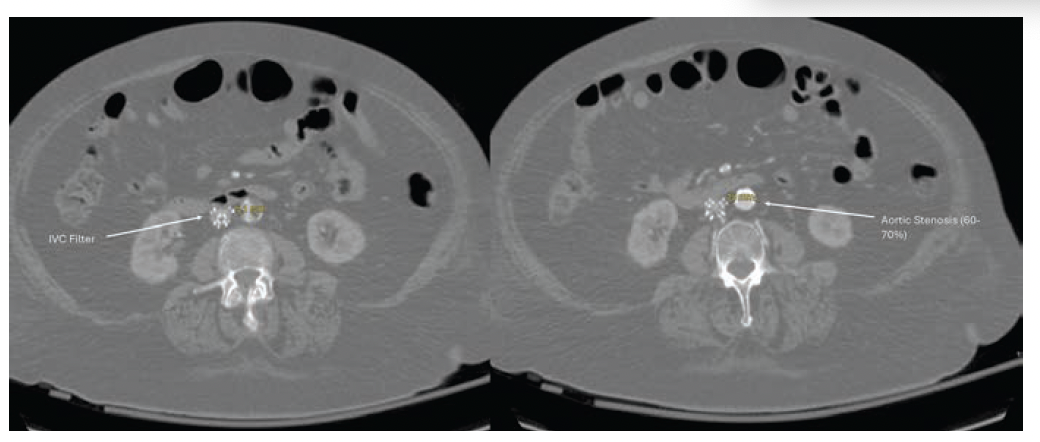

- CT-Guided Lumbar Sympathectomy: A Palliative Approach for Intractable Ischemic Rest Pain in Chronic Limb-Threatening Ischemia

When revascularization isn’t an option, pain control becomes the priority in advanced CLTI. This article highlights computed tomography (CT)-guided lumbar

sympathectomy as a fast, minimally invasive palliative strategy that can dramatically relieve ischemic rest pain—even in frail, high-risk patients. A valuable reminder that symptom relief and quality of life still matter when limb salvage is no longer possible.